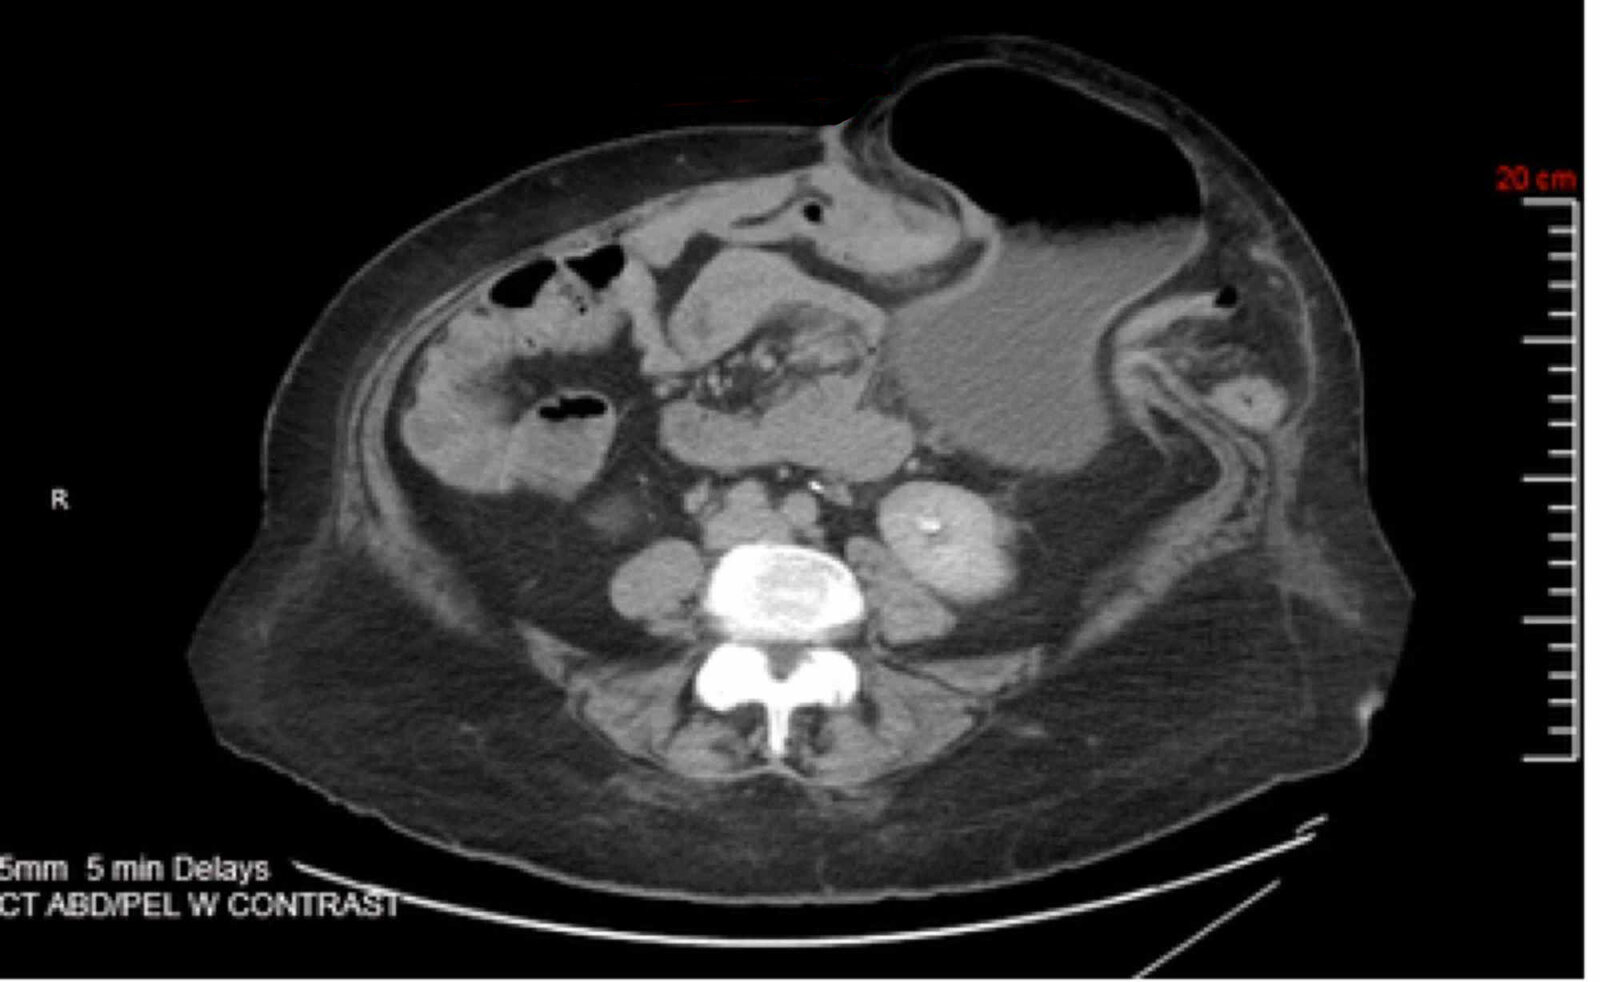

• CT abdomen

• Sensitive imaging study for suspected bowel obstruction or strangulation [10]

• Typically performed with both IV and PO contrast (unless contraindicated because of obstruction)

• Can facilitate planning for complex hernia repair [23]

Findings

• Direct visualization and quantification of the fascial defect(s)

• Presence of viscera in the hernial sac

• Strangulated hernia: signs of visceral ischemia [25]

• Obstructed hernia: radiological signs of mechanical bowel obstruction